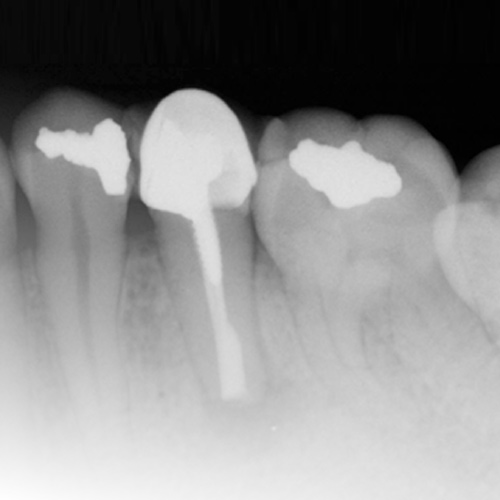

Endodontic Updates

Wednesday, March 22, 2023

This Compendium eBook offers a continuing education (CE) article on unseparated fractures and their diagnostic complexities. This eBook also includes a case report article on the use of cone-beam computed tomography for the analysis of atypical root canal anatomy. Download to earn 2 FREE CE...

Endodontic Advances

Friday, October 21, 2022

This Compendium eBook offers a continuing education (CE) article that examines the most recent guidelines of the American Association of Endodontists and the American Dental Association regarding the prescription of antibiotics, and outlines the best choices for antibiotic treatment for bot...

Current Topics in Endodontics

Monday, September 24, 2018

This special Compendium eBook presents two articles on topics in endodontics. The first article, a continuing education course with a quiz for 2 credits, examines various steps of endodontic treatment and how, from a restorative standpoint, treatment can be improved for better long-term predictabili...